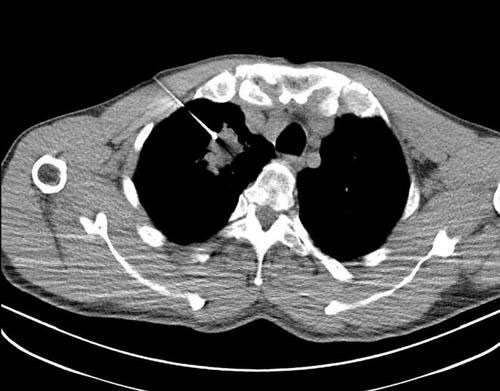

CT引导下胸部病灶穿刺活检术

CT引导下胸部穿刺活检目的是以最小的创伤准确获得肺内病变或胸膜病变组织,通过穿刺活检后的病理检测了解肺癌的具体细胞学类型、分化程度、靶向药物治疗敏感程度等相关信息,为临床进一步诊疗提供依据。

检查前影像科医师评估患者身体状况,仔细评价患者胸部增强CT影像,判断其是否适宜进行CT引导下穿刺,是否为CT引导下肺穿刺活检术的适应症,明确执行该手术对患者的诊疗意义,初步确定穿刺路径及取材部位。